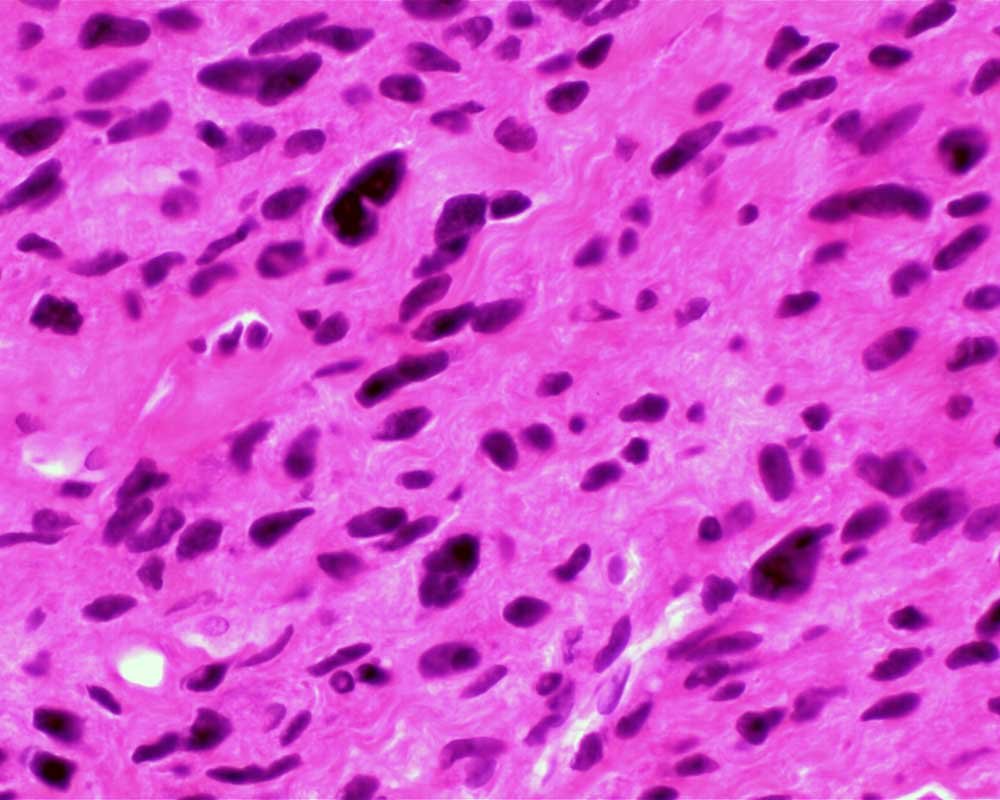

Case: ThighMass2

Final Diagnosis: